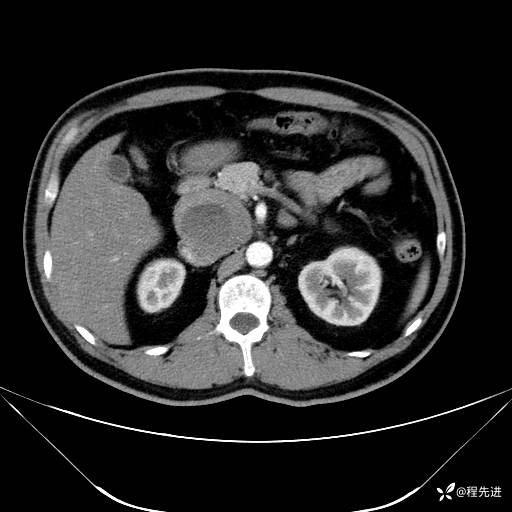

【腹盆】特别精彩病例|发现腹膜后肿物1月余

患者年龄:42岁

主诉:发现腹膜后肿物1月余

现病史:患者1月余前查体,行超声检查提示:后腹膜囊实性肿块;慢性胆囊炎伴胆囊内结石;无腹痛腹胀,不伴腹泻发热等;偶感腰背部酸痛。

CT平扫+增强: